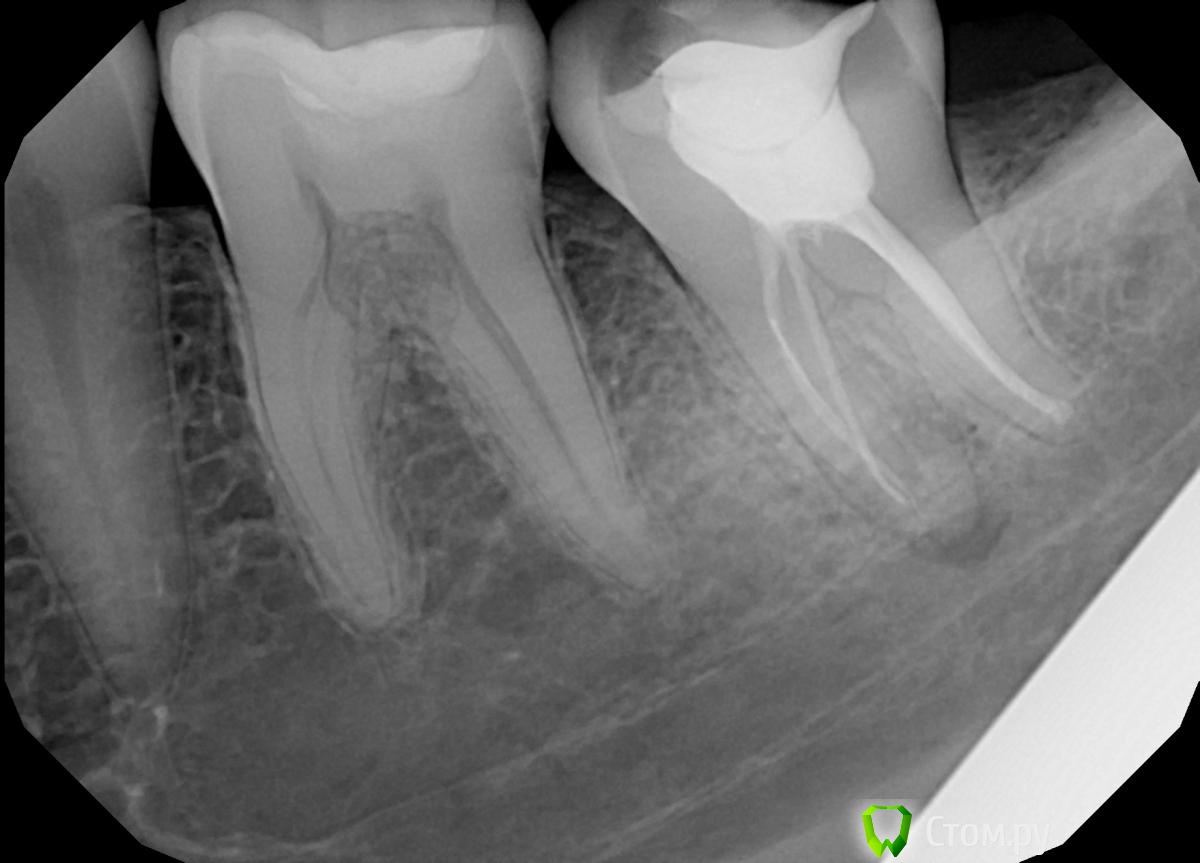

Valerkaa Опубликовано 25 сентября, 2014 Поделиться Опубликовано 25 сентября, 2014 Всем добрый вечер! Родственнице делали снимки 3.7, в кадр еще и 3.6 попал .Сама, к сожалению, во рту посмотреть не могу, она живет в другом городе. Но со слов, жалоб никаких, да и внешне тоже все спокойно. На что это похоже? У меня что-то никаких мыслей кроме внутренней резорбции или чего-то такого нет. Доктор отправляет родственницу на МРТ. У кого какие мысли? Ссылка на комментарий

AlexanderGudkov Опубликовано 25 сентября, 2014 Поделиться Опубликовано 25 сентября, 2014 Всем добрый вечер! Родственнице делали снимки 3.7, в кадр еще и 3.6 попал .Сама, к сожалению, во рту посмотреть не могу, она живет в другом городе. Но со слов, жалоб никаких, да и внешне тоже все спокойно. На что это похоже? У меня что-то никаких мыслей кроме внутренней резорбции или чего-то такого нет. Доктор отправляет родственницу на МРТ. У кого какие мысли? Лучше на клкт) Ссылка на комментарий

Паращук Роман Опубликовано 25 сентября, 2014 Поделиться Опубликовано 25 сентября, 2014 Да а с чего ей там быть? Кт сегментарное сделайте и все будет видно. Ссылка на комментарий